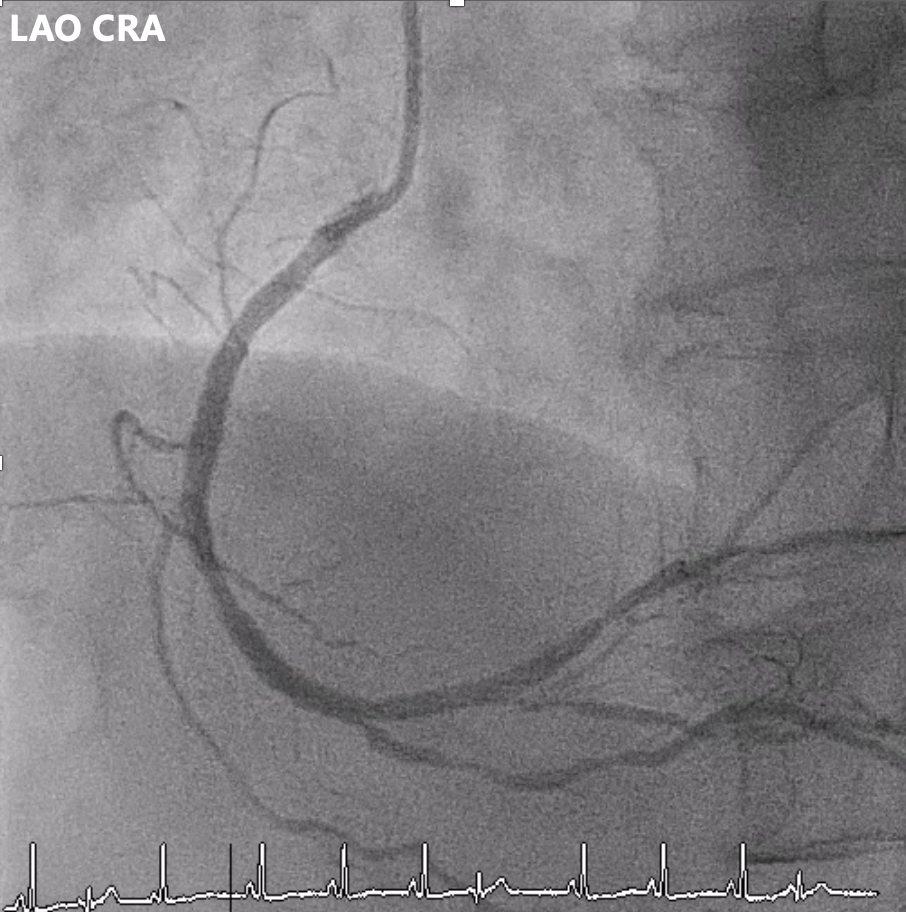

Angiography showed multivessel atherosclerosis with the LAD being the most critical lesion. The mid LAD had tubular eccentric 70–80% stenosis with a Medina (0,1,1) bifurcation and a mid-segment CTO (~2 cm, blunt end). DB1 had 70–80% ostial stenosis with 50–70% diffuse disease, and DB2 had a short CTO with distal collateral flow from DB1. Other vessels had non-critical or moderate diffuse disease.

Left RAO CRA.mp4